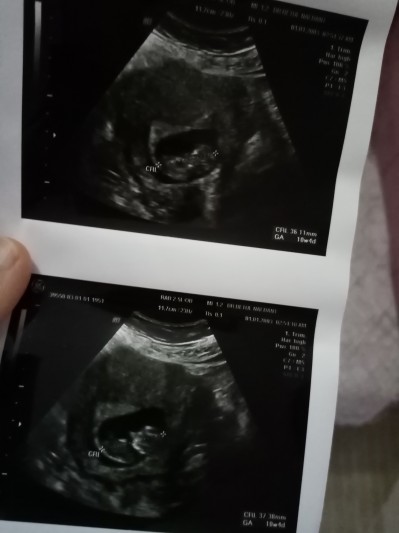

10+4 cinsiyet belli mi bayanlar

Gebelik haftası 11+2

Çok karanlık bir ultrason hiçbir şey görünmüyor.

Canım benimde 11+ 1 ama daha çok erken.benim doktorum öyle dedi.bence burda kafani karıştırma.hic belli bile değil bizim yunanistanda 3d ile çekim yapıyorlar okadar belli vücudu ama daha cinsiyet organı oluşmuş bile değil dedi doktorum